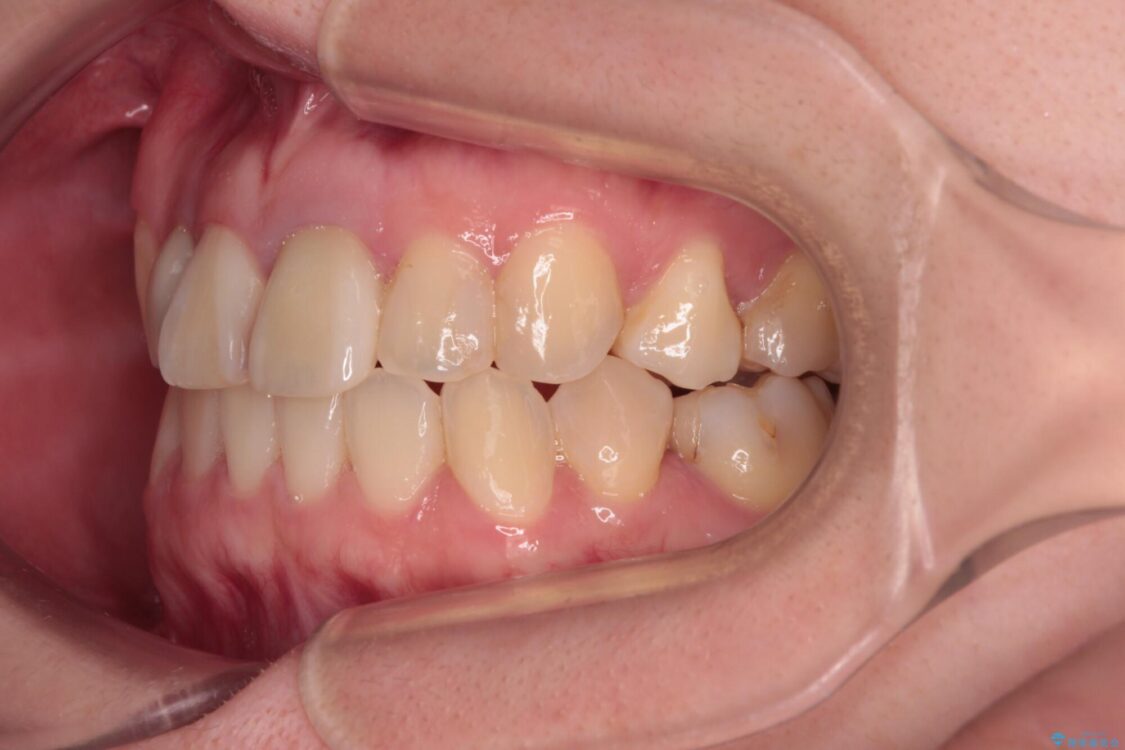

治療後

• 虫歯治療ついでに歯並びの後戻りを改善 インビザラインによる矯正治療 治療後画像

後戻りは軽度であり、インビザラインにて歯列を整え、その後にオールセラミッククラウンにて補綴治療を行うこととしました。

治療後について

ご家庭やお仕事の都合で通院が途絶えた時期があり、治療は長期間となりましたが、無事に終えることができました。